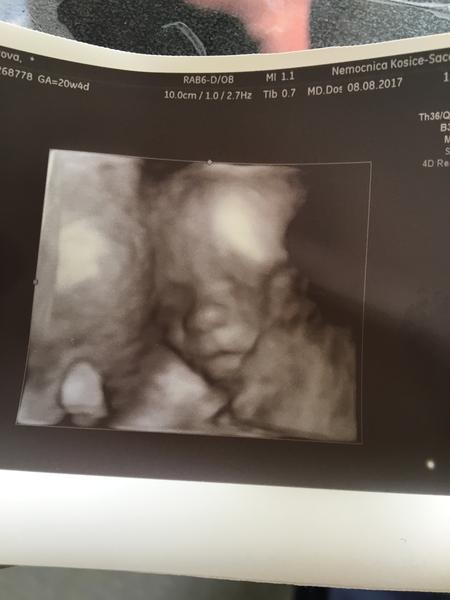

Babulky a my čakáme druhu slečnu som sa zamilovala do nej ešte viac cez sono ako pózovala a ukázala tvaricku..len nám neukázal pohlavie iba povedal ale prvé čo má zaujimalo bolo či je zdravá a všetko mame Ok..váži 360g že vyzerá že bude väčšia babulka veľmi sa teším a želám to zažiť každej čakatelke